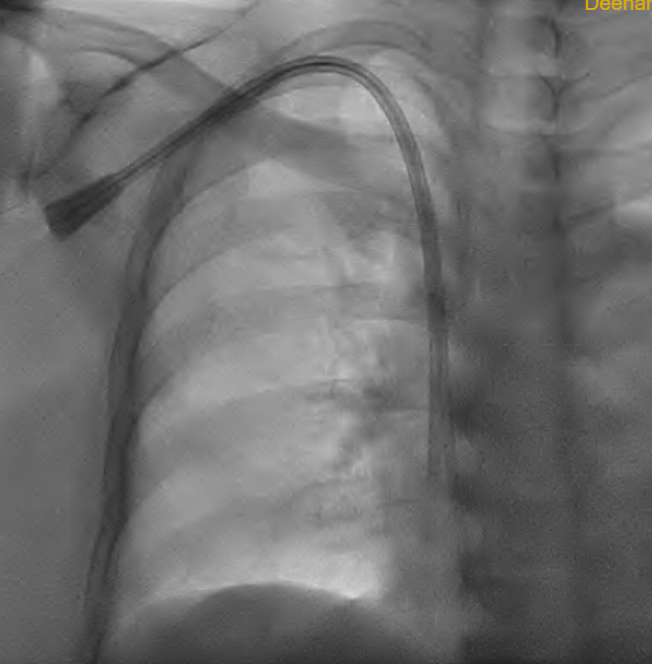

One of the most crucial procedures performed by Interventional Radiologists is dialysis fistula salvage, also known as fistuloplasty.

Guided by advanced imaging, a tiny catheter is threaded into the narrowed portion of the fistula. A balloon is then gently inflated, reopening the vessel and restoring blood flow.

In many cases, this minimally invasive procedure can save a failing fistula and keep dialysis running smoothly.